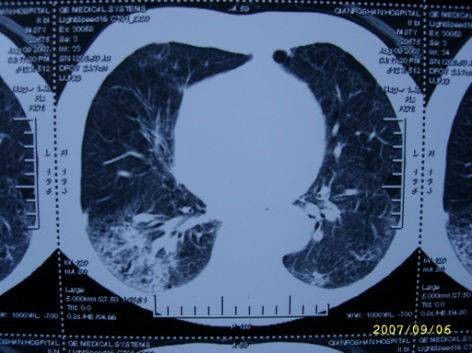

治疗前